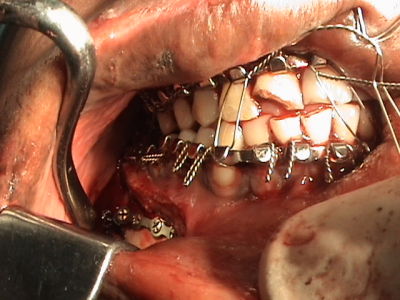

•    Internal fixation of maxilla & mandible

•    Open reduction and internal fixation of maxilla and mandible